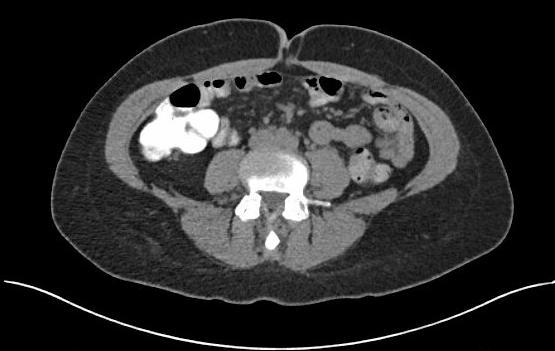

Three years after successful abdominal wall reconstruction at age 51, the patient developed abdominal discomfort that she normally associated with her menstrual cycle and dismissed the pain. The pain eventually progressed to consistent right sided lower abdominal pain and she presented to our hospital with leukocytosis of (13.7) and a CT-scan of the abdomen that demonstrated appendicitis with no evidence of rupture or abscess (Figure 3).

Figure 3 CT scan of the abdomen at the time of acute appendicitis at a level below the umbilicus at the level of the appendix showing reapproximation of the rectus abdominis muscles. The Strattice underlay mesh is visible and in position intraperitoneally. A functional abdominal wall is restored.